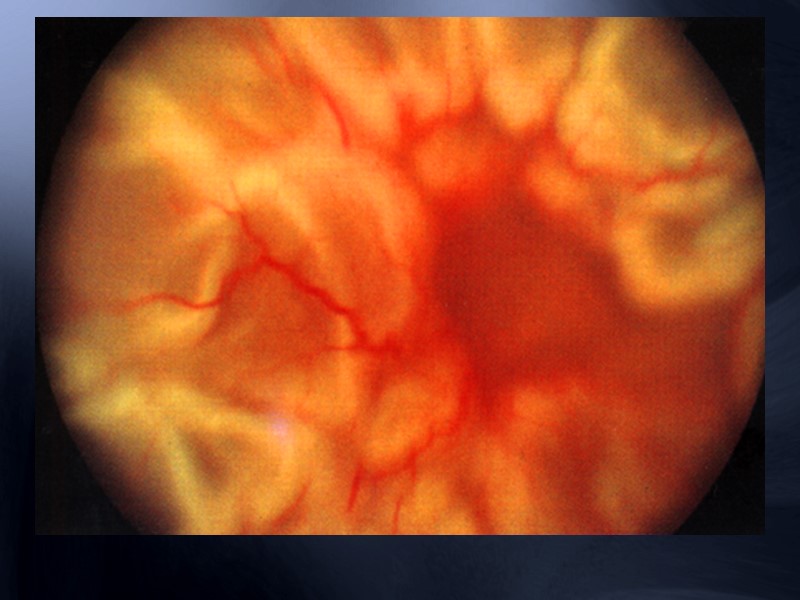

Картина « раздавленного помидора » Проявления: усиление венозного дерева, повышение извитости и расширение капилляров, ретинальные геморрагии, ватообразные экссудаты, ретинальные геморрагии, макулярный отёк. Гемофтальм, отёк ДЗН могут быть.

Тромбоз центральной вены сетчатки